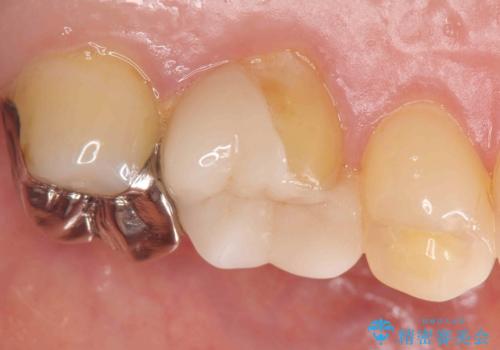

- 右下の奥歯がうずくとのことで来院されました。

根管治療を行った後、セラミックのかぶせ物を装着します。

- 右下6 精密根管治療(大臼歯・リトリートメント):143,000円 土台:22,000円 仮歯:11,000円 ジルコニアクラウン:121,000円 合計297,000円費用は治療当時の料金となります

治療後は症状も改善し、半年後の経過も良好です。